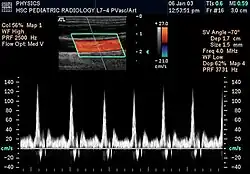

La información dópler se representa gráficamente con un dópler espectral, o bien como una imagen usando Doppler direccional o un power Doppler (Dópler no-direccional). La frecuencia Dópler cae en el rango audible y puede escucharse utilizando altavoces estéreo, produciendo un sonido pulsátil distintivo.[cita requerida]

El dópler color es, esencialmente, el sistema computacional incorporado a la máquina de ultrasonido. Este asigna unidades de color, dependiendo de la velocidad y dirección del flujo sanguíneo. Por convención, se ha asignado el color rojo para el flujo hacia el transductor y el azul para aquel que se aleja.[3]

La mayoría de los dispositivos modernos usan la ecografía dópler pulsátil, produciendo un dópler con flujo en color, para medir flujos en el centro o en la periferia de un vaso sanguíneo.[4] Los dispositivos de ondas pulsadas transmiten y reciben una serie de impulsos, por lo general recibiendo la información antes de enviar el siguiente impulso. El cambio de frecuencia de cada pulso se ignora, sin embargo los cambios de fase relativa de los pulsos se utilizan para obtener el cambio de frecuencia, puesto que la frecuencia es la tasa de cambio de dicha fase. Las principales ventajas del dópler pulsátil sobre la variedad de onda continua es que se obtiene información de la distancia (el tiempo entre la transmisión y recepción de los impulsos puede ser convertida en una distancia sabiendo la velocidad del sonido). La desventaja del dópler pulsátil es que las mediciones pueden sufrir de aliasing. El término "ultrasonido dópler" o "sonografía dópler", ha sido aceptado para referirse tanto a la versión pulsátil como el sistema continuo a pesar de los diferentes mecanismos por los cuales cada uno mide el flujo.[cita requerida]